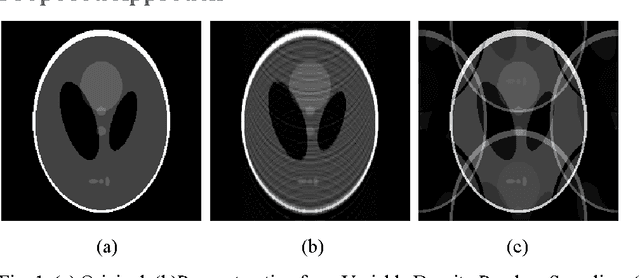

In this work we address the problem of real-time dynamic MRI reconstruction. There are a handful of studies on this topic; these techniques are either based on compressed sensing or employ Kalman Filtering. These techniques cannot achieve the reconstruction speed necessary for real-time reconstruction. In this work, we propose a new approach to MRI reconstruction. We learn a non-linear mapping from the unstructured aliased images to the corresponding clean images using a stacked denoising autoencoder (SDAE). The training for SDAE is slow, but the reconstruction is very fast - only requiring a few matrix vector multiplications. In this work, we have shown that using SDAE one can reconstruct the MRI frame faster than the data acquisition rate, thereby achieving real-time reconstruction. The quality of reconstruction is of the same order as a previous compressed sensing based online reconstruction technique.